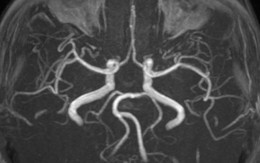

Thai ngoài tử cung là hiện tượng trứng đã thụ tinh nhưng không nằm trong tử cung mà phát triển ở một vị trí khác, như ống dẫn trứng (thường gặp nhất), buồng trứng, cổ tử cung, hay trong ổ bụng.

95% thai ngoài tử cung nằm ở ống dẫn trứng. Bởi vì ống dẫn trứng rất nhỏ và không thể mở rộng tốt để phù hợp với sự phát triển của phôi thai, phôi thai không thể phát triển đầy đủ, vì vậy hầu hết sẽ xảy ra hiện tượng vỡ.

Một số phôi có thể được tách ra khỏi thành ống và phóng vào khoang bụng, được gọi là sinh non thai ngoài ống dẫn trứng (sinh non ở ống dẫn trứng chảy vào khoang bụng), vỡ ống dẫn trứng hoặc sinh non đều có thể gây ra xuất huyết lớn trong ổ bụng, đe dọa đến tính mạng.